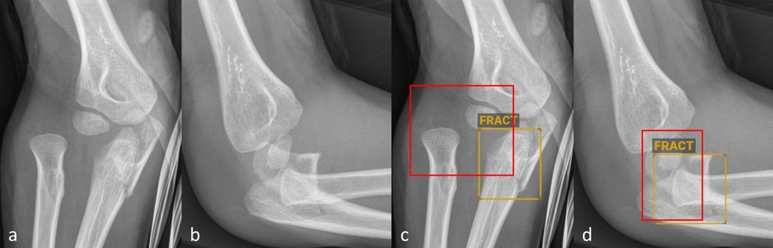

fracture en tore métaphysaire distale identifiée par l'IA

Figure 1 : Radiographies antéro-postérieures (a et c) et latérales (b et d) de l’avant-bras d’un enfant âgé de cinq ans sans (a–b) et avec (c–d) marquage diagnostique réalisé par BoneView. Le logiciel d’IA a identifié et marqué correctement la fracture en tore métaphysaire distale du radius et de l’ulna.

© Altmann-Schneider I, Kellenberger CJ, Pistorius SM, Saladin C, et al. Artificial intelligence-based detection of paediatric appendicular skeletal fractures : performance and limitations for common fracture types and locations. Pediatr Radiol. 2024 ; 54(1):136-145. http://creativecommons.org/licenses/by/4.0/ La figure correspond à une partie de l’original sans autre modification.

Globalement, il existe relativement peu d’études publiées sur le diagnostic de la fracture par l’IA chez les enfants et adolescents. Les quelques études de validation réalisées en externe des logiciels disponibles dans le commerce décrits ci-dessus montrent toujours une sensibilité et une spécificité élevées (majoritairement supérieures à 90 %) des logiciels testés [4–6]. Les études varient toutefois fortement en termes de nombre total de radiographies analysées (entre 300 et 2634), de nombre de radiographies par groupe d’âge et d’évaluation des résultats. Seule une étude classe les résultats en fonction du type de fracture spécifique, mais ne tient pas compte de la localisation anatomique [6]. Dans une étude réalisée à l’hôpital pédiatrique universitaire de Zurich, nous avons récemment testé la précision diagnostique du logiciel d’IA BoneView (Gleamer) dans un ensemble de données comptant 1000 radiographies de localisations de fractures fréquentes chez les enfants (avant-bras, coude et jambe inférieure) [7]. Pour la totalité des fractures, des taux de sensibilité et spécificité similaires à ceux de précédentes publications sur le même logiciel ont été déterminés [6]. La figure 1 montre l’exemple d’une fracture en tore de l’avantbras correctement identifiée par le logiciel d’IA. Le classement selon le type de fracture a toutefois présenté d’importantes limitations. Ainsi, des fractures en flexion de l’avant-bras n’ont pas été identifiées de manière fiable. Par ailleurs, le taux de détection des avulsions de l’apophyse styloïde de l’ulna, des fractures en tore du radius proximal et des fractures de l’olécrane était nettement plus bas (< 80 %) par rapport aux autres fractures de l’avantbras. Dans la partie inférieure de la jambe, un taux de détection inférieur des « toddler’s fractures » (74 %) et fractures survenues sur trampoline (66 %) a été observé. Au niveau des coudes, seules les fractures supra-condyliennes complètes et les fractures du col radial ont été identifiées avec un taux de détection supérieur à 80 %. La détection d’épanchements articulaires au niveau du coude comme signe indirect de fracture était seulement modérée. Les luxations de l’articulation du coude n’ont pas été identifiées avec fiabilité (figure 1). Pour résumer, il est à retenir que les résultats – parfois discrets, mais extrêmement pertinents – susceptibles d’échapper à un oeil moins avisé ne peuvent pas non plus être détectés de façon fiable par le logiciel.